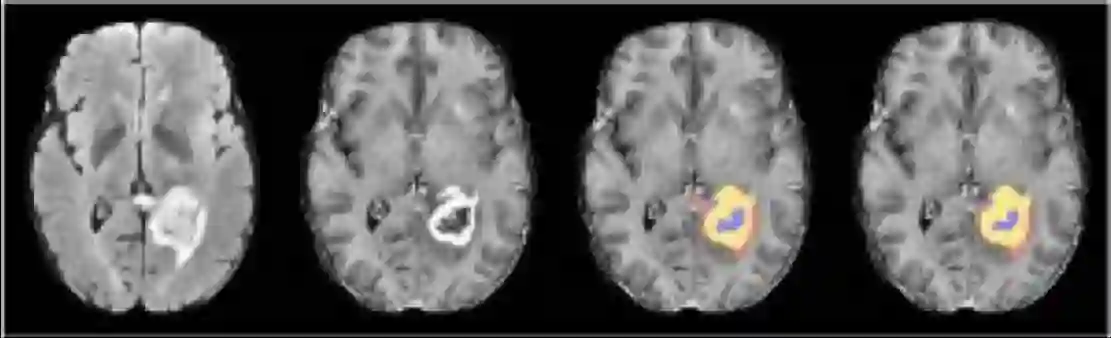

脑出血区域自动标记